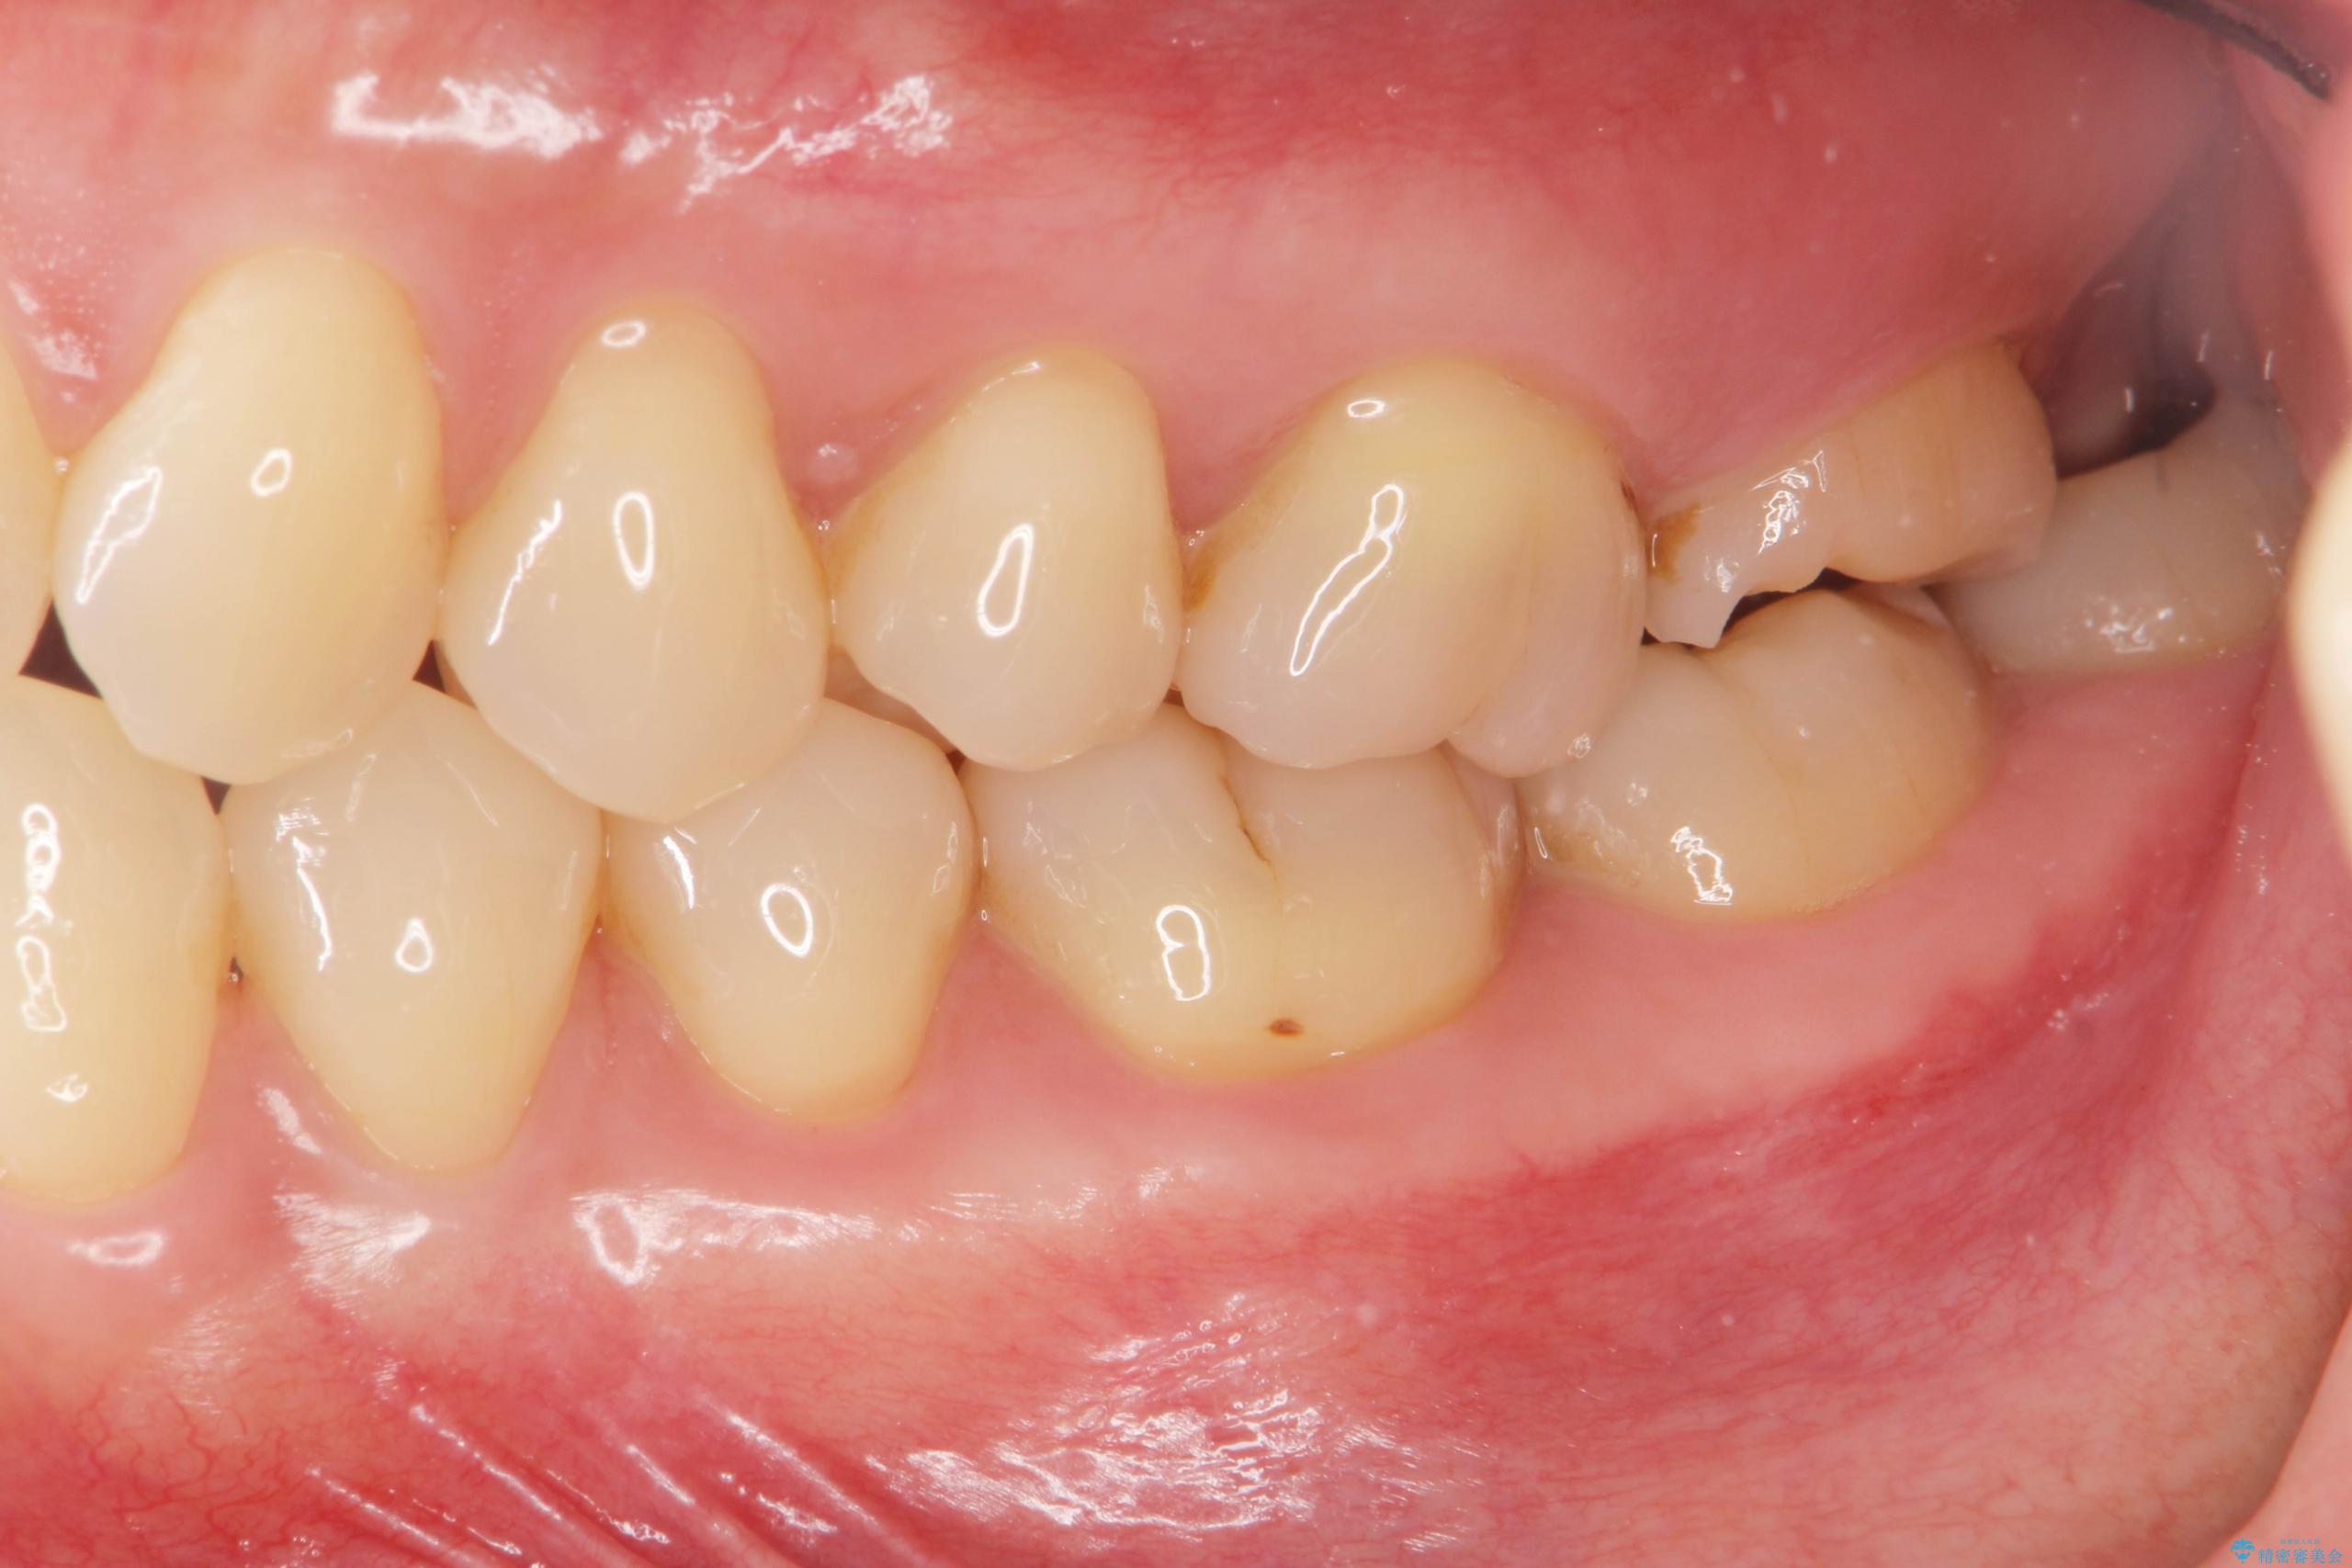

噛むと歯が疼いて痛い、と根管治療を希望され来院されました。

精査した結果、上顎奥歯は歯が割れてしまっており、根管治療ではなく抜歯の対象でした。

治療前

【噛むと歯が疼く】歯牙破折からのインプラント治療 治療前画像 【噛むと歯が疼く】歯牙破折からのインプラント治療 治療前画像 【噛むと歯が疼く】歯牙破折からのインプラント治療 治療前画像 【噛むと歯が疼く】歯牙破折からのインプラント治療 治療前画像 【噛むと歯が疼く】歯牙破折からのインプラント治療 治療前画像 【噛むと歯が疼く】歯牙破折からのインプラント治療 治療前画像 【噛むと歯が疼く】歯牙破折からのインプラント治療 治療前画像